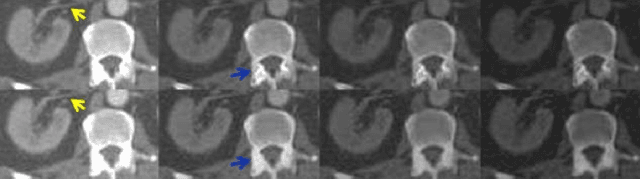

Abstract:Energy-resolving computed tomography (ErCT) has the ability to acquire energy-dependent measurements simultaneously and quantitative material information with improved contrast-to-noise ratio. Meanwhile, ErCT imaging system is usually equipped with an advanced photon counting detector, which is expensive and technically complex. Therefore, clinical ErCT scanners are not yet commercially available, and they are in various stage of completion. This makes the researchers less accessible to the ErCT images. In this work, we investigate to produce ErCT images directly from existing energy-integrating CT (EiCT) images via deep neural network. Specifically, different from other networks that produce ErCT images at one specific energy, this model employs a unified generative adversarial network (uGAN) to concurrently train EiCT datasets and ErCT datasets with different energies and then performs image-to-image translation from existing EiCT images to multiple ErCT image outputs at various energy bins. In this study, the present uGAN generates ErCT images at 70keV, 90keV, 110keV, and 130keV simultaneously from EiCT images at140kVp. We evaluate the present uGAN model on a set of over 1380 CT image slices and show that the present uGAN model can produce promising ErCT estimation results compared with the ground truth qualitatively and quantitatively.